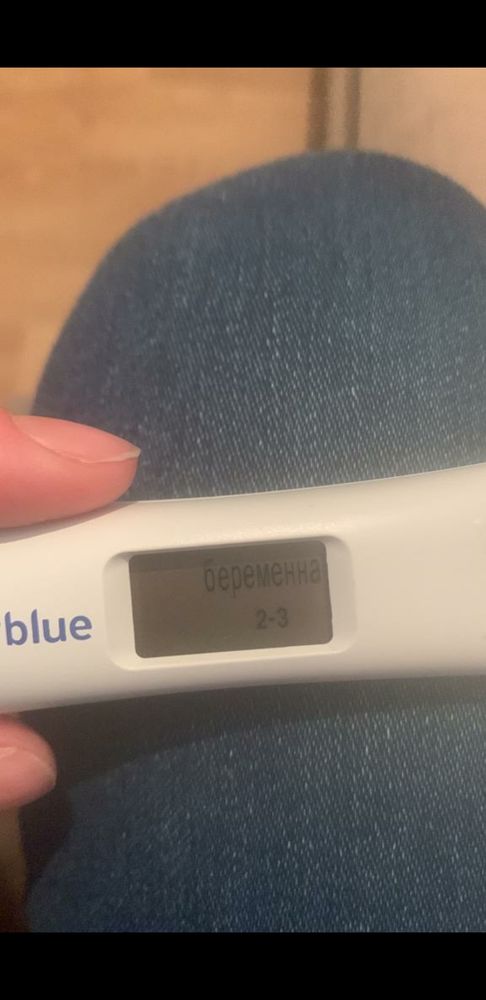

Лимоночка, Получается что этот тест от 11.01.23 показывает верно, просто где-то прочитал что Clear Blue Digital не точно показывает.

Лимоночка, Получается что этот тест от 11.01.23 показывает верно, просто где-то прочитал что Clear Blue Digital не точно показывает.

Gennady Babansky, этот тест показывает результат по уровню хгч, 2-3 недели эмбриональных это 4-5 акушерских как раз. А правильно или нет не знаю, думаю погрешность есть, но в целом наверное верно

Кстати когда она сделала этот тест 11 января, который показал что больше 2ух недель уже, а 13 Января уже в поликлинике врач что-то нащупала рукой в боку у неё она говорила и сказала что ну вот он, что-то такое

Лимоночка, Нашлась фотография это было 9 января, плохо видно правда, посмотрел в интернете динамику тестов это вроде как 13-15 дпо

А этот 11 января вечером

В большинстве случаев все так и говорят что зачатия и тд в декабре было, а начинаешь смотреть учебники, приложения по беременности (каркуляторы и тд) ютуб видео и начинает рисоваться другая картина, что типа вот допустим если бы зачатие было 1го то до 16 января ещё 15 дней грубо говоря, и вот около 5 дней она добирается по трубам, потом крепится и растёт, как пишут 1 мм в день, и так совпадает что увидели 16 января, пя 7,5 мм. Тест на беременность был 11 января клеар блу диджитал показал 2-3 недели, 9 января 2 плоски яркие обычный тест, но оба теста делались вечером, не утром, 13 января врач гинеколог что-то нащупала в боку, типа вот есть там что-то, я понимаю я спрашиваю одно и тоже постоянно у всех и получаю разные но более менее хорошие и обнодежиаающие ответы что это декабрь, спасибо за это людям больше, мне кажется что у меня паранойя уже начинается, я очень сильно хочу чтобы всё было так как Вы пишите что это 25 декабря! В некоторых случаях мне говорили что овуляция могла быть позже и что после овуляции можно забеременеть, вот поэтому наверное переспрашиваю всё, извините если что!

А имеет ли значение в какое время делается тест на беременность утром или вечером, тесты просто делались вечером и вот тот который Clear Blue Digital показал 2-3 недели 11 Января, а знакомая сказала что он реагирует на уровень хгч и что сегодня он может показать 1-2 недели, а типа завтра утром уже 2-3(

Марина, Вот ещё пишут про тест Clear Blue Digital, как Вы считаете может такое быть?

Вот эти тесты один 9 Января вечером, другой 11 января и тоже вечером

Вот эти тесты один 9 Января вечером, другой 11 января и тоже вечером

Понятно вообщем, а Вы не знаете Clear Blue Digital, точно показывают?